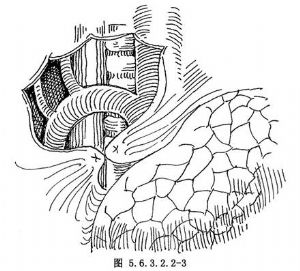

食管中段牵引型憩室的手术治疗方法有:憩室切除术、憩室翻入埋缝术、食管支气管瘘缝扎修补术以及食管部分切除食管胃吻合术等。憩室并发癌变或不能逆转的瘢痕狭窄,应行食管部分切除或较为彻底的憩室切除。术式的选择取决于患者的全身状况及病变本身的情况。严格掌握手术适应证和准确细致的手术操作,避免不必要的手术创伤,是保证手术成败的重要措施。